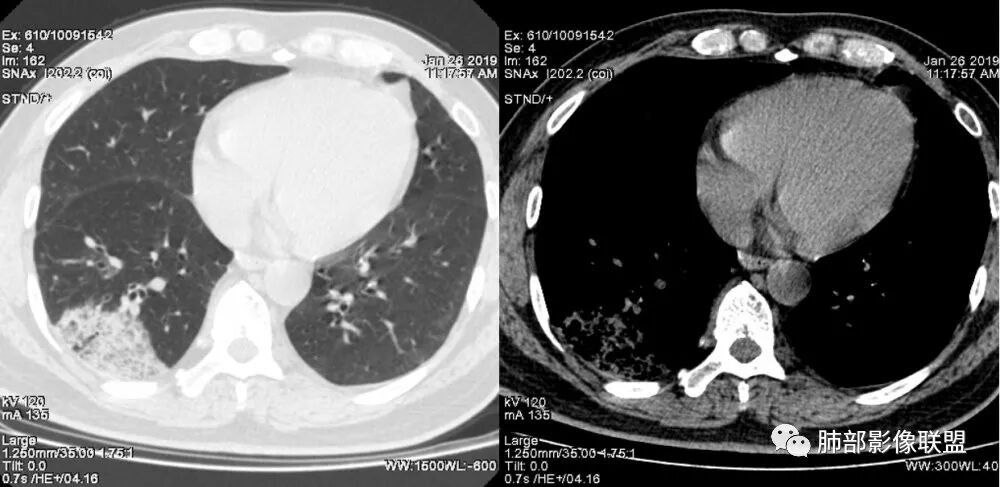

老年女性,右肺下叶沿胸膜下大片状高密度影,外周磨玻璃影,边界较清,内可见蜂窝征及支气管充气征,考虑肺炎型肺癌。

老年女性,咳嗽咳痰病史,右肺下叶大片磨玻璃实变影,胸膜下分布,支气管进入后扩张、僵直,磨玻璃影边界清楚,考虑粘液腺癌。鉴别肺炎。

右肺下叶基底段靠胸膜实变/磨玻璃混杂密度影,边界清楚,内见多发空泡(蜂窝样趋势改变?); 临床:咳嗽咳痰,无发热、胸痛; 考虑腺癌:无发热,感染性病变不首先考虑;部分层面形态类楔形,鉴别肺栓塞

中年女性,咳嗽咳痰。右肺下叶片状高密度影,部分实性密度,周围见边界清晰磨玻璃影,内见小空泡,实性区部分支气管堵塞,有重力效应,考虑肺炎型肺癌,建议查痰脱落细胞。

老年人,右肺下叶斑片状阴影,病灶有膨胀性,边缘可见磨玻璃影,其边界清晰,内见僵硬的支气管,部分支气管扩张,首先考虑占位性病变,粘液性腺癌可能。鉴别感染性病变,后者边缘多有收缩性改变或者平直,内部支气管走形自然。

1.本例病灶较大片混杂密度影,胸膜下分布为主(未沿着支气管分布),该分布特点可见于大叶性肺炎、干酪性肺炎、淋巴瘤及粘液腺癌等。可惜未提供增强扫描图像。

2.病灶示中央实变区,周围GGO,可见明显小叶间隔增厚,GGO边界清楚,应当考虑到恶性病变的可能性。肺炎因炎性水肿及渗出,影像上边界常模糊不清,注意早期粘液腺癌可出现似清非清的边界。粘液腺癌因粘液成份较多,密度一般偏低,纵隔窗病灶常会消隐或范围会明显缩小,这不同于炎性实变。

3.病灶内支气管走形略显僵直,侧支少(粘液阻塞),也符合肺腺癌的枯树枝征。而大叶性肺炎的支气管是管壁光整、通畅、自然,结核的支气管常常壁增厚,甚至狭窄后扩张;